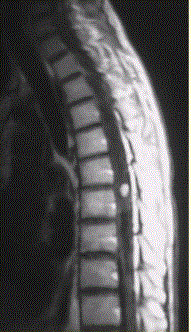

问题 患者女,45岁,胸部不适。影像学检查结果如下图所示。 病变的诊断为

选项 A.星形细胞瘤 B.室管膜瘤 C.脊髓空洞 D.髓内寄生虫 E.成血管细胞瘤 F.脊髓内转移瘤

答案 E